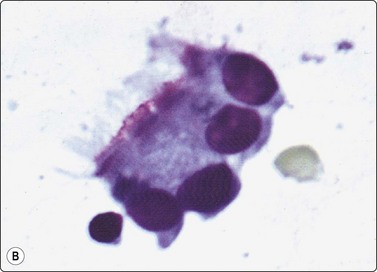

Liver cell adenoma (Fig. 10.13)

Cytodiagnosis of this entity can hardly be made with confidence by cytology alone and a core biopsy can provide additional architectural information. The cytological pattern must be correlated with clinical presentation and radiological findings.115 A solitary liver mass found in a young woman with a history of oral contraceptive usage is most likely a hepatocellular adenoma, whereas a mass in an older patient with cirrhosis is more likely either a regenerative nodule or a hepatocellular carcinoma.

image

Fig. 10.13 Liver cell adenoma

Poorly cohesive epithelial cells resembling hepatocytes, bland nuclei, Kupffer cells but no bile duct epithelium (A, H&E, IP; B, Pap, HP); (C) Corresponding tissue section (H&E, IP).

Criteria for diagnosis46

Moderate to markedly cellular smears arranged in clusters or tissue fragments,

Monotonous cells resembling normal hepatocytes with pale or vacuolated cytoplasm,

Absence of bile duct epithelium.

Problems and differential diagnoses

Adenoma is difficult to differentiate from other low grade hepatocellular lesions, ie FNH and well differentiated hepatocellular carcinoma.

The differences in cytological patterns between adenoma and well-differentiated carcinoma can be subtle and will be discussed in the section on hepatocellular carcinoma. The cytoplasm is more abundant, less fragile and better defined with more distinct cell borders in adenoma, the nuclear : cytoplasmic ratio is consistently low, and single, bare neoplastic nuclei are less apparent (Fig. 10.13). Marked anisokaryosis is not a feature. Adenoma and FNH both comprise benign hepatocytes. In the absence of abundant bile duct epithelium, which favors FNH, distinction between them is not possible.41,106